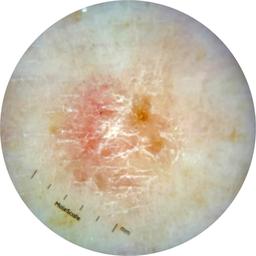

ISIC_7193897

1979 x 1979

Clinical

Field Value

acquisition_day 251

age_approx 65

anatom_site_1 Lower extremity

anatom_site_general lower extremity

concomitant_biopsy False

diagnosis_1 Benign

diagnosis_confirm_type single image expert consensus

family_hx_mm False

image_manipulation instrument only

image_type dermoscopic

lesion_id IL_3780211

patient_id IP_3751325

personal_hx_mm True

sex female